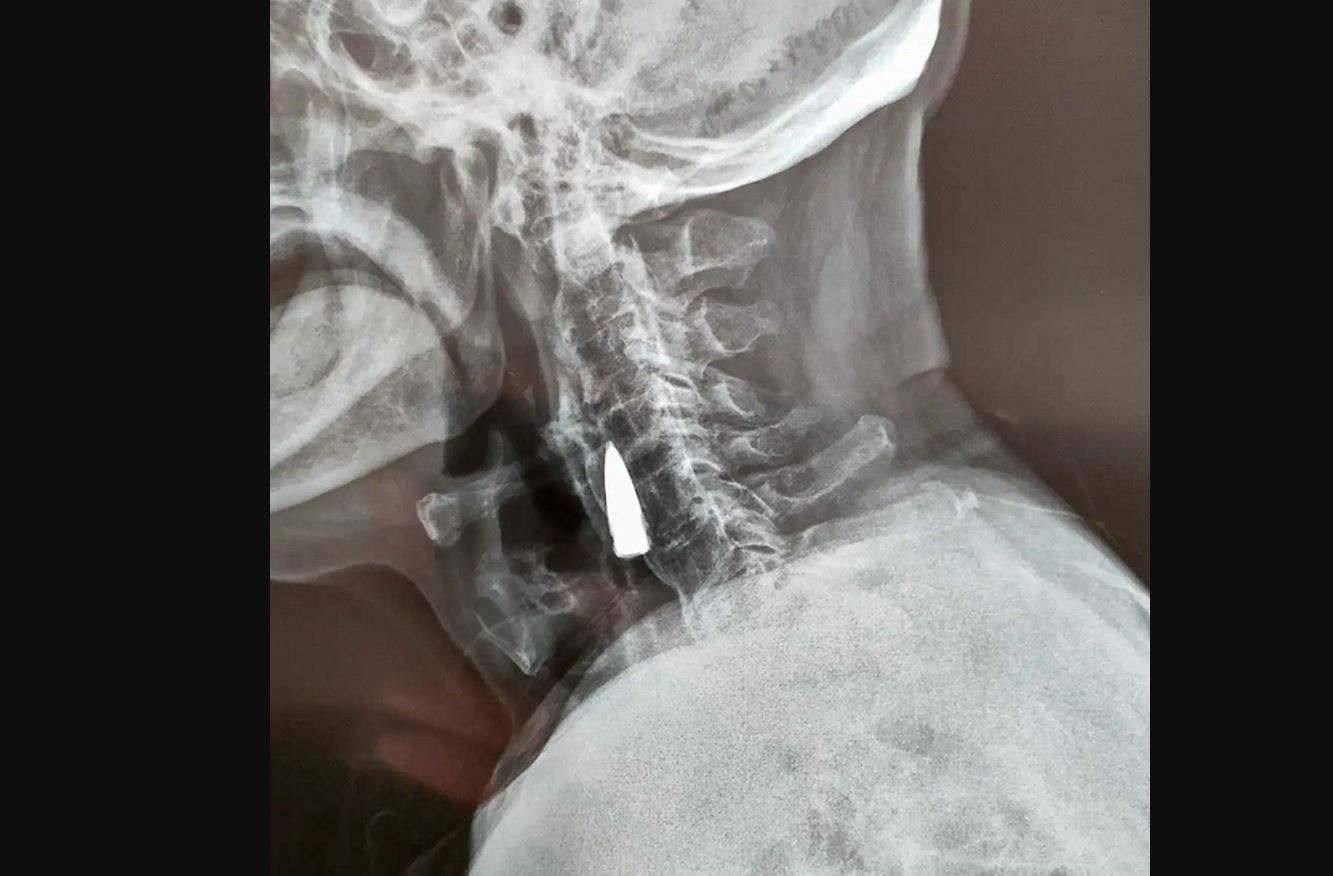

وكشفت الأشعة للجندي السابق تشاو هو وعمره قارب 95 عامًا عن مفاجأة صادمة عندما تبين أنه يحمل رصاصة في رقبته منذ 77 عامًا.

وكانت الرصاصة استقرت في جسده منذ الحرب العالمية الثانية، لكنه لم يكن يعلم حتى بوجودها حتى اكتشفها الطاقم الطبي في مستشفى في شاندونغ بالصين بالصدفة.

ودهش الخبراء الطبيون من أن الرصاصة لم تسبب أية مشاكل للرجل على الرغم من وجودها في رقبته لمدة 77 عامًا.

وبسبب تموضع الرصاصة الحساس، وأيضا بسبب عمر الرجل قرر الأطباء عدم إزالة الرصاصة لأن إخراجها من شأنه أن ينطوي على جراحة محفوفة بالمخاطر.